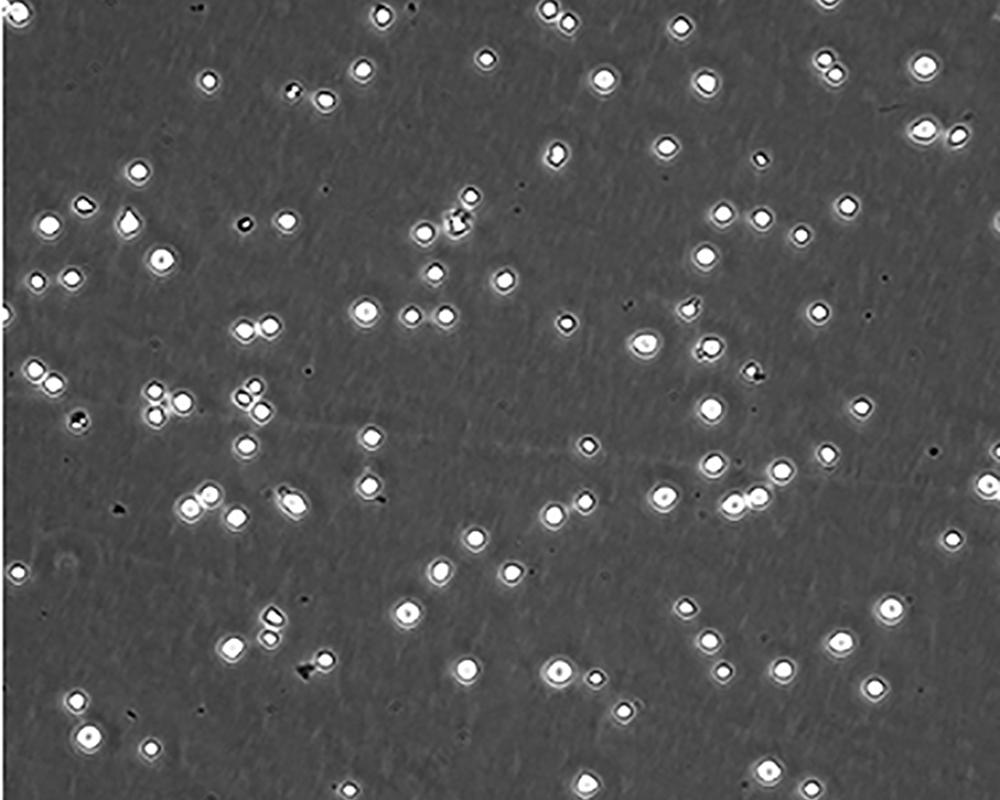

生長特性 suspension

形態(tài)特征 lymphoblast

細(xì)胞描述 CEM/C1是人T細(xì)胞白血病細(xì)胞株CCRF-CEM(見ATCC CCL-119)具有喜樹堿抗性的衍生株。1991年細(xì)胞株選擇并亞克隆了對CPT的抗性。細(xì)胞表現(xiàn)出對CPT類似物水溶性的托泊替康和非水溶性的9-氨基-CPT及10,11-亞甲二氧基-CPT具有交叉抗性。CEM/C1細(xì)胞對CPT的敏感性較母系CEM細(xì)胞低31倍。CEM/C1細(xì)胞表現(xiàn)非典型的多藥抗性和轉(zhuǎn)換拓補(bǔ)異構(gòu)酶I催化活性。對CPT的抗性維持6個月以上。